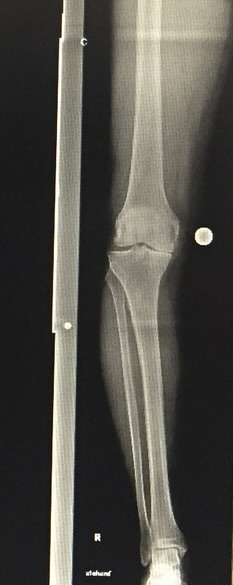

- Προχωρημένη οστεοαρθρίτιδα γόνατος

- Αποτυχία συντηρητικής αγωγής

- Ιδιαίτερη ανατομία ή προηγούμενες επεμβάσεις